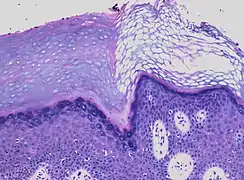

- In contrast, hyperkeratosis (pictured) may also show a heterogeneous stratum corneum, but a preserved granular layer is seen.